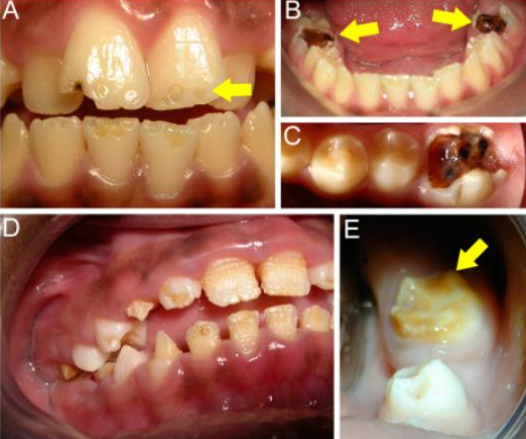

Vitamin A and D deficiency

Enamel hypoplasia